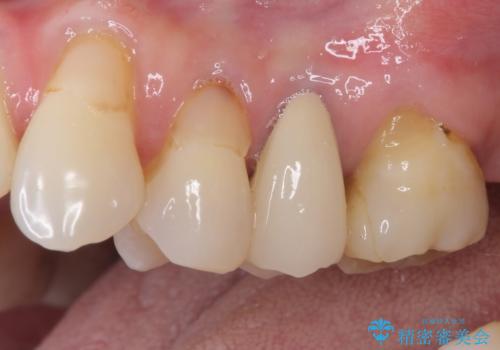

- 歯肉が退縮したためにクラウンの縁や歯根が見えてしまっていることを気にして来院された患者様です。

仮歯に変えた後にオールセラミッククラウンにて補綴することとしました。

強い咬合力や磨きすぎなどにより、歯根が見えてしまったり、金属の縁が見えてしまったりし、審美障害を引き起こすことがあります。

歯根が変色してしまうと、歯肉越しに歯根の黒い色が透けてしまうことがあり、この点についてはどうにも施しようがないため、患者様には事前のご理解いただきました。